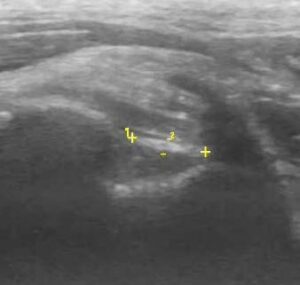

- 28/06 ecografia = lesione muscolare di 3° grado

Mentre nel sano si evidenziano le fibre muscolari ipoecogene frammiste al perimisio ecogeno, nel malato si vede l’area anecogena, un vero e proprio buco: le miofibrille sono strappate. Attorno all’area anecogena un alone iperecogeno, rappresenta l’infiammazione. È presente anche una notevole atrofia muscolare.

Gracile destro, spessore 1.98 cm

SPESSORE 1,98

Gracile sinistro, spessore 1.60 cm

SPESSORE 1,60

Persiste area povera di fibre muscolari.

Nel complesso muscolo lievemente atrofico ma non presenti segni di infiammazione o di sclerosi.

Ottima risoluzione per uno strappo muscolare, in genere non si ha la restitutio ad integrum ecograficamente.